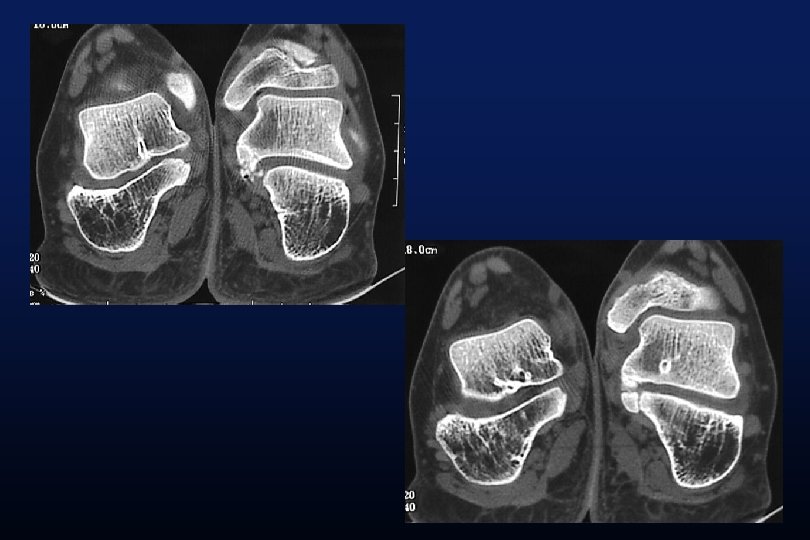

LES SYNOSTOSES DE L ’ARRIERE PIED Coalitions Tarsiennes (Tarsal Coalitions)

CALCANEO NAVICULAIRES (60%) TALO CALCANEENNES Synostoses et coalitions tarsiennes chez l'enfant. Étude de 68 cas chez 47 patients Ph. Rouvreau, J. C. Pouliquen, J. Langlais, C. Glorion, G. de Cerqueira Daltro The Too-Long Anterior Process Calcaneus: A Report of 39 Cases in 25 Children and Adolescents Pouliquen, J. C. M. D. ; Duranthon, L. D. M. D. ; Glorion, Ch. M. D. ; Kassis, B. Journal of Pediatric Orthopaedics Volume 18(3) June 1998 333 -336

Comfort 1998 Résection Coalition / surface sous talienne > 1/3 75% de mauvais résultats < 1/3 77% de bons résultats.